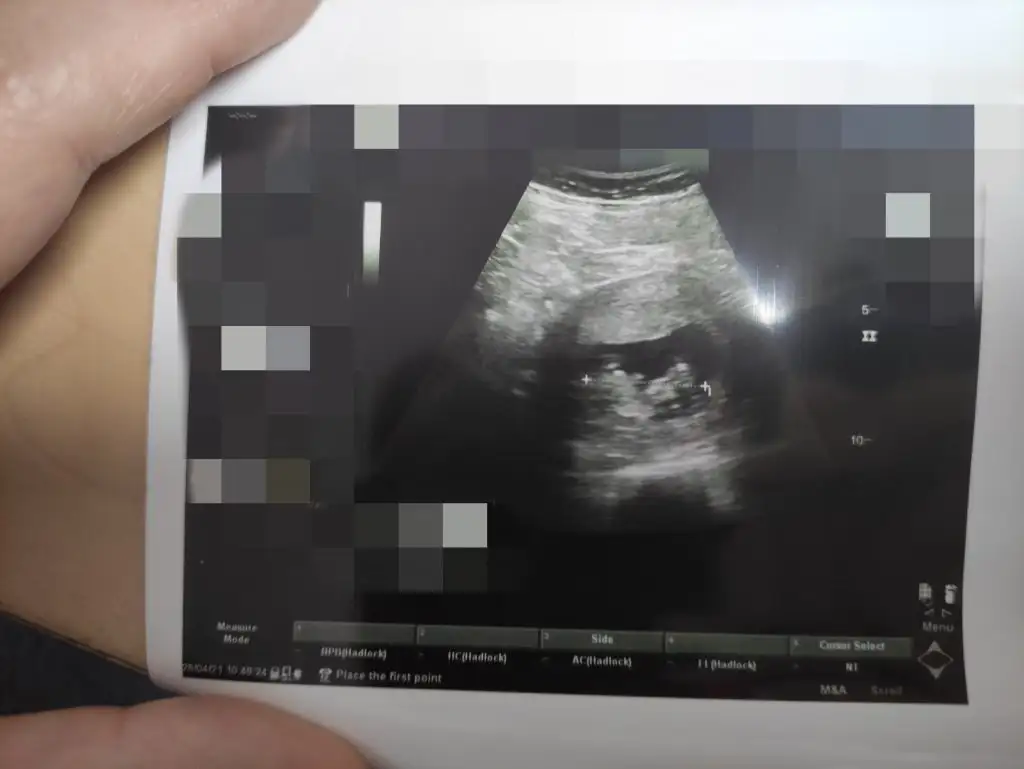

Benim bebeğime de bakar mısınız 12+4 günlük burada doktor cinsiyetini göremedii sizce nedir

Eklentiler

• 7B4DCC87-F158-4690-9BEE-AF5E7C4673AA.webp

69,6 KB · Görüntüleme: 60

• F804C3CA-BCC8-45DC-AEDA-959083DC5EE7.webp

47,3 KB · Görüntüleme: 60